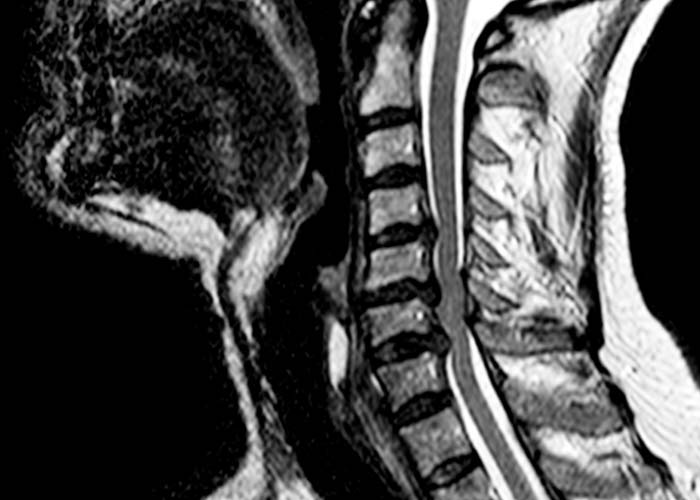

• Resonancia Magnética Cervical: voluminosas hernias discales cervicales C4-C5, C5-C6 y C6-C7 con estenosis del canal espinal central más acusado en C5-C6 y mielopatía cervical C5-C6.

Se trata de una afectación medular (mielopatía) por estenosis del canal medular en relación a la compresión de la médula por las hernias cervicales.